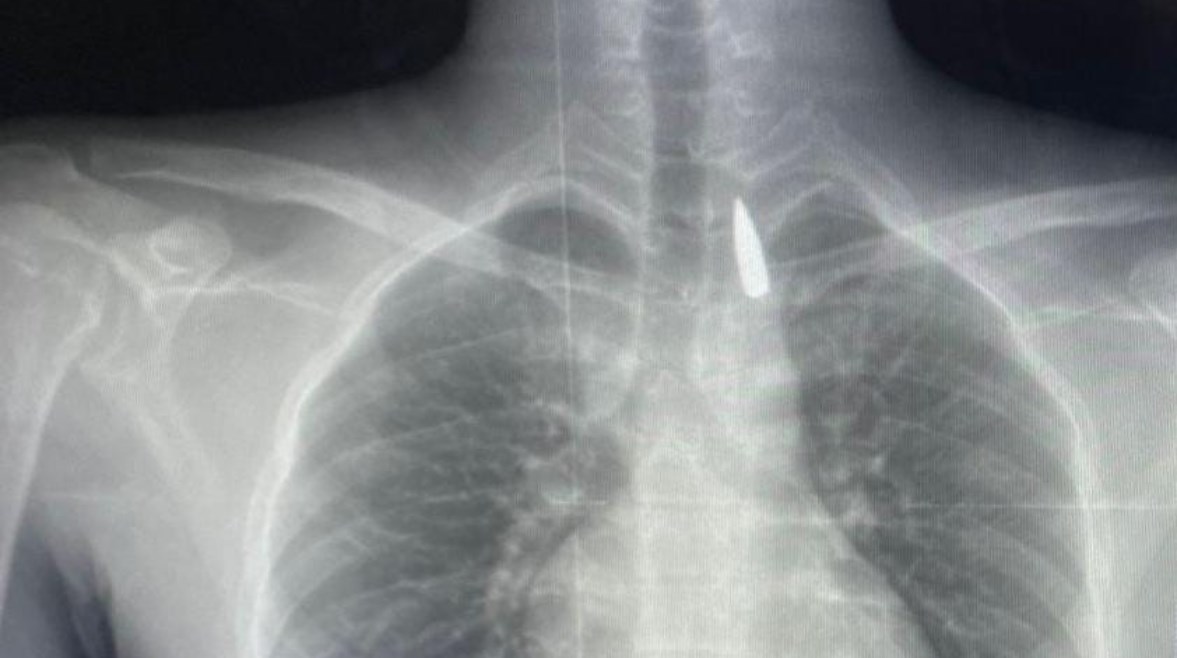

وأوضح الدكتور تامر عبد الله، عميد كلية الطب ورئيس مجلس إدارة المستشفيات الجامعية، أنه في يوم 21 أكتوبر 2025، تمكن فريق من أطباء قسم جراحة القلب والصدر والتخدير والمعاونين من إجراء جراحة دقيقة بالغة الخطورة لأحد المرضى المحجوزين من قطاع غزة، والذي كان قد تعرض لإصابة بطلق ناري في الرأس منذ فترة، استقر المقذوف على إثرها داخل تجويف القفص الصدري قرب الشريان الأورطي، وهو أكبر وأهم شرايين الجسم والمسؤول عن تغذية جميع الأعضاء الحيوية، وأضاف أن الفريق الطبي، رغم دقة الحالة وتعقيدها، نجح في استخراج المقذوف بأمان بعد عملية جراحية نادرة استمرت عدة ساعات داخل المستشفى الجامعي الجديد، حيث خضع المريض بعدها للرعاية الطبية اللازمة، وحالته حاليًا مستقرة وتحت المتابعة الدقيقة من الفريق المختص.